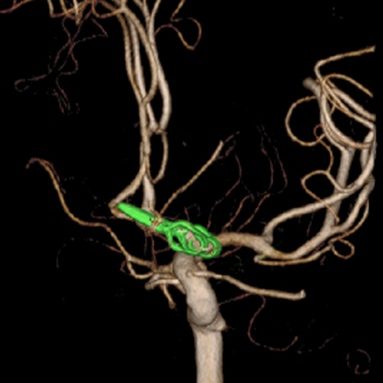

当科で治療した年々大きくなった大型脳底動脈瘤の3次元脳血管撮影像です。脳動脈瘤と周囲の血管の状態が非常によく分かるため、術前に十分な検討が可能でした。

正常の脳底動脈の血流は維持されている。